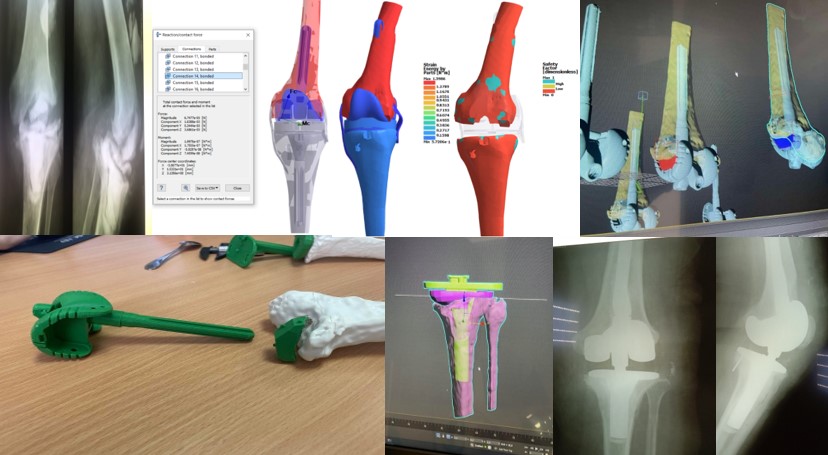

В своїй роботі ми класифікацією кісткових дефектів ложе нестабільнокористувалисяго протеза колінного суглоба за AORI (Anderson Orthopaedic Research Institute, USA), 1997 де автори виділяють 3 типа кісткових дефектів

Тип 1 – інтактна кістка (intact metaphysealbone) – невеликі кісткові дефекти, зазвичай без пошкодження кортикальної кістки. Характеризується нормальною кісткової структурою і збереженням губчастої і кортикальної кістки метафиза, нормальним рівнем суглобової лінії. позначаються як F1 – для стегнової кістки і Т1 – для великогомілкової.

Тип 2 – пошкоджена кістка (damаged metaphyseal bone) – характеризується втратою губчастої і кортикальної кісткової маси метаепіфізів, без заповнення якої неможливе створення надійної опори для компонентів ревізійного імплантату і відновлення анатомічного рівня суглобової лінії. (F2 А та F2 Б – для стегнової і Т2 А та Т2 Б – для великогомілкової кісток)

Тип 3 – дефіцит кістки (deficient metaphyseal segment) – характеризується вираженою втратою губчастої і кортикальної кісткової маси метаепіфіза, без компенсації якої неможливе створення опори для компонентів ревізіційного імплантату і відновлення нормального рівня суглобової лінії. Дефекти частіше поширюються до надвиростків і вище на стегнової кістці або до горбистості і нижче на великогомілковій кістці. (F3 А та F3 Б – для стегнової і Т3 А та Т3 Б– для великогомілкової кісток)

МОДЕЛЮВАННЯ НАВАНТАЖЕНЬ В ПРОТЕЗОВАНОМУ КОЛІННОМУ СУГЛОБІ

Етапи проектування індивідуальних аугументів для ревізійного ендопротезування колінного суглоба

Паціент М., Міно-вибухове поранення кісток колінного суглобу. Мегадефекти стегнової та Великогомілкової кістки 3 ст по класифікації (Aori). остіоміеліт. Стан після заміщення дефектів спейсером з антибіотиком

Виконане операційне втручання: Видалено спейсери з антибіотиком, резекція за допомогою індивідуальних навігаційних систем та імплантовано ендопротез з індивідуальними аугментами